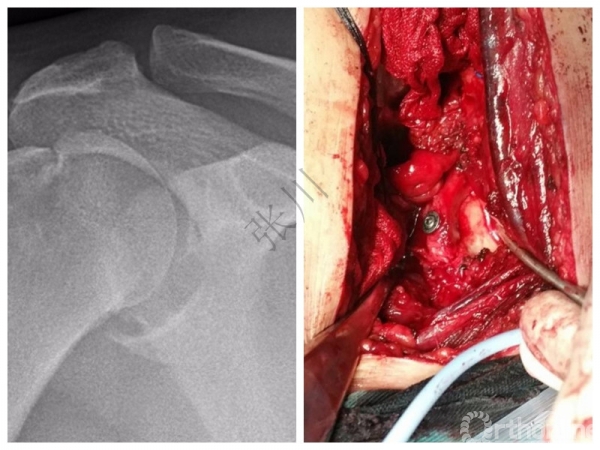

1.手术类型:切开/微创?

手术方式:关节镜?可行

3. 术前诊断、手术方案与术式

2.方法:Sugaya技术全关节镜下带线锚钉修复,两例应用Remplissage技术,3例应用5点钟和后外侧入路